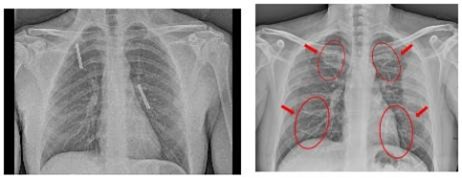

Table 2 shows the chest X-rays from three categories: pneumonia, tuberculosis and normal chest X-rays. The pneumonia image highlights red circles to indicate where the infection has occurred in the lungs. The image of tuberculosis reveals the usual signs, including abnormal conditions in the lungs. On a normal chest X-ray, the lungs are healthy and show no signs of abnormality. Many DL models in medical diagnostics were trained with these images.

Pneumonia Image | Tuberculosis Image | Normal Chest X-ray |

![]() | ![]() | ![]() |